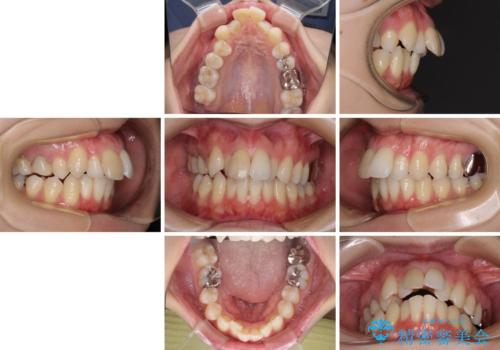

- 口を閉じたときに飛び出してしまう上顎前歯を気にして来院された患者様です。

上下の咬み合わせは上顎歯列全体が歯1本分前にずれている状態であり、さらに上顎歯列はV字型に尖っていたため、上下前歯は全く接触していない状態でした。

上顎左右第一小臼歯を抜去して、ワイヤー装置にて口元の突出感を改善するよう矯正治療を行うこととしました。

上顎前歯の歯軸が顕著に改善され、非常に口の閉じやすい歯列に仕上げることができました。